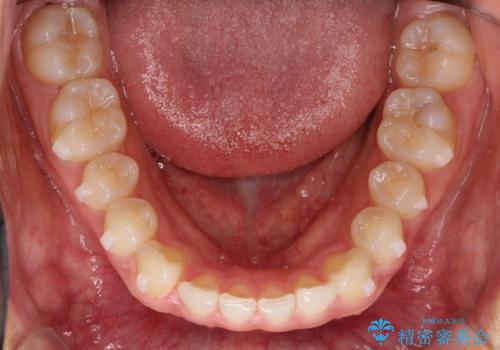

すきっ歯のインビザラインによる目立たない矯正

- すきっ歯を治したいとのことで来院されました。

上下ともに前歯に隙間がありました。

目立たない装置をご希望のためインビザラインで矯正治療を行うこととしました。

使用時間を守っていただけたので、スムーズに治療を終わることができました。